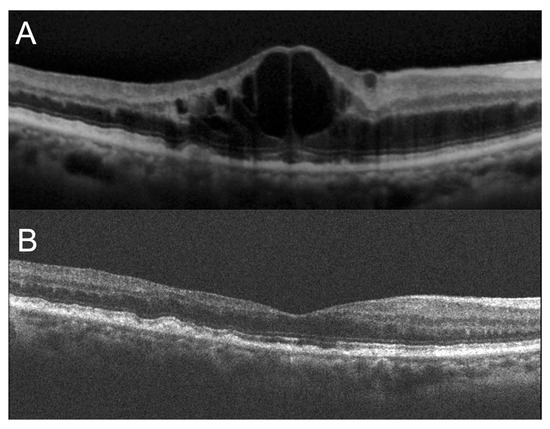

Representative Cases